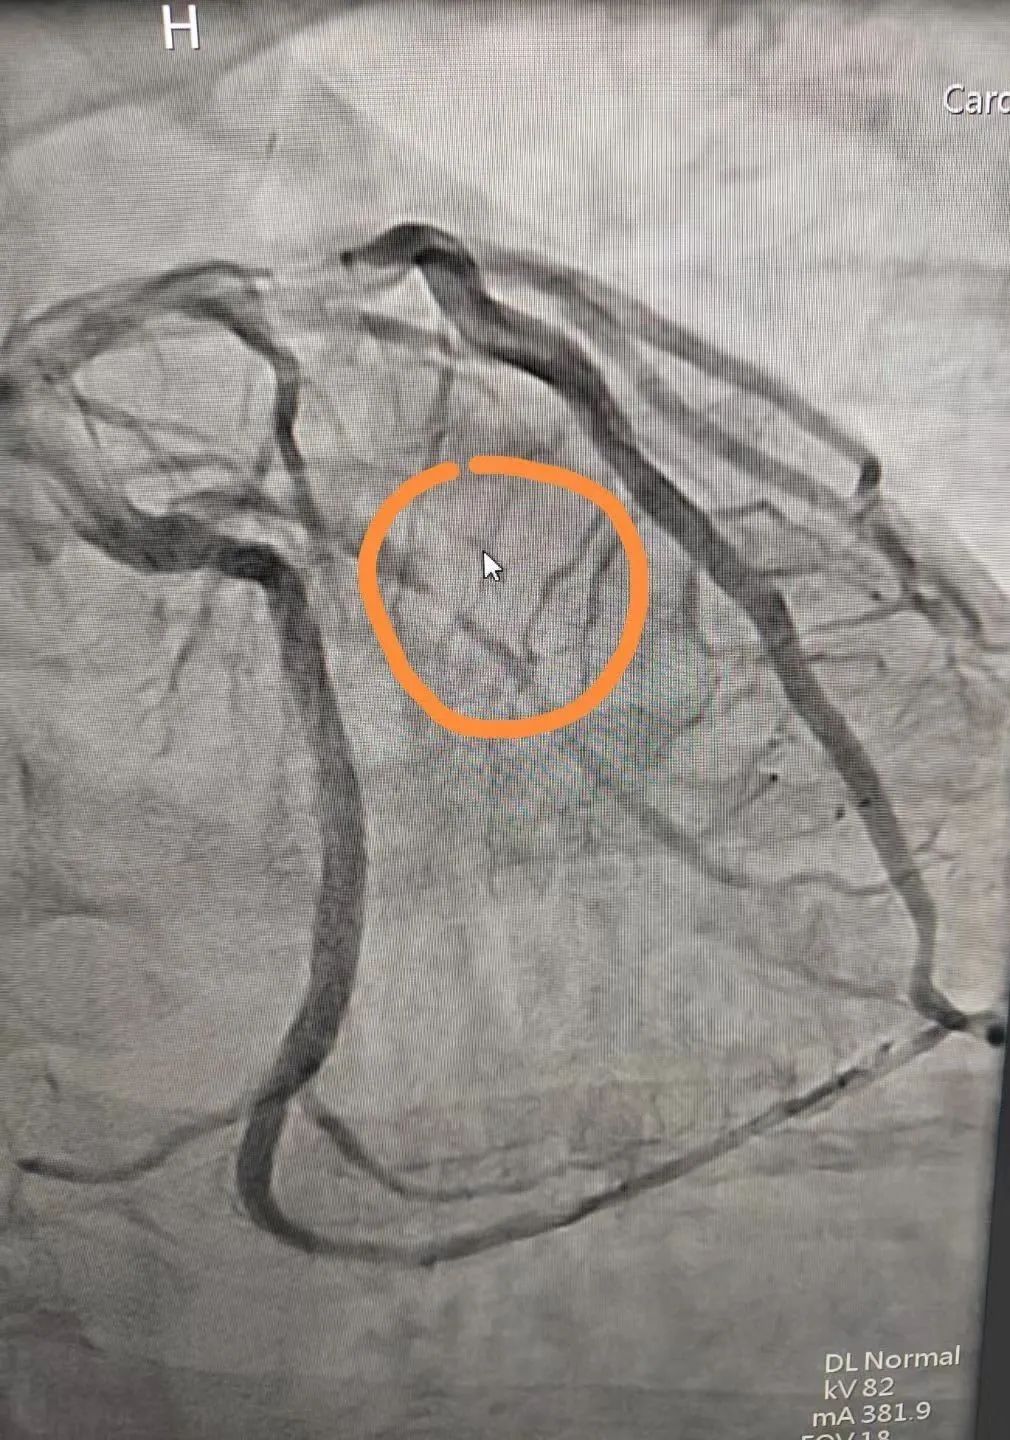

图为造影提示:第一钝缘支次全闭塞。